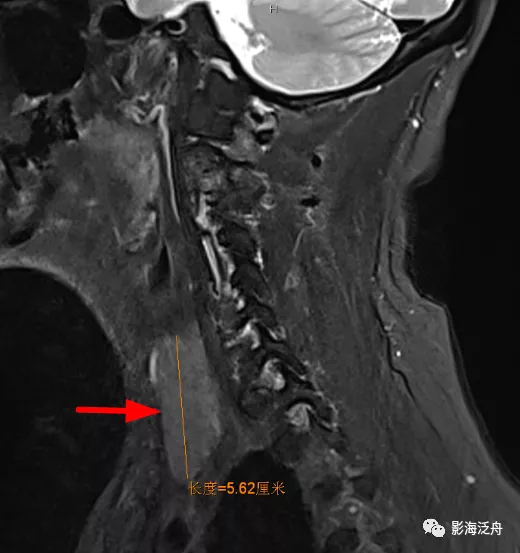

乳腺癌术后患者,枢椎骨质信号异常,随访证实为骨转移。随着肿瘤患者越来越多,行颅脑MR检查排除脑转移的检查也逐渐增多,不要只顾着在脑子里面找转移灶,周围的结构也应该观察一下。

矢状位上另一个需要观察的就是齿状突的高度,异常增高往往是颅底凹陷症导致的(红线为钱氏线)。